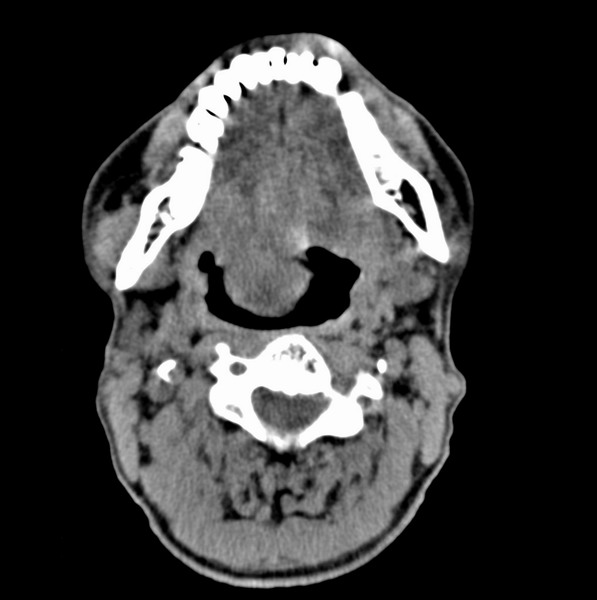

标题: CT19620:舌根肿物

男、60、舌根肿物。

舌垂直肌和横肌影处肿块影,边缘不规则,咽腭扁桃体及舌下间隙脂肪影消失,病变侵及口咽。

考虑-----舌根癌

舌跟软组织肿块,较大有坏死,钙化。结合年龄一般是恶性肿瘤。

舌根部较大软组织肿块,其内见坏死低密度区及钙化影;考虑舌根癌可能。